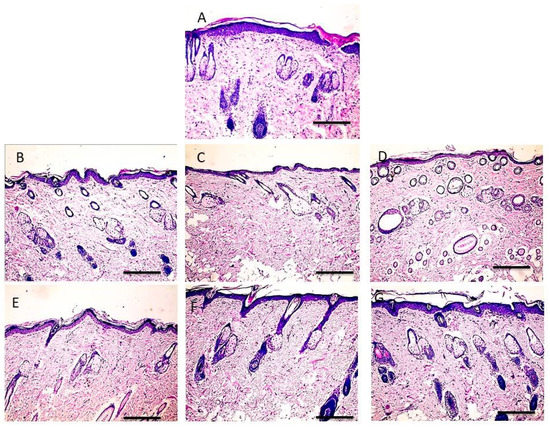

3.10. Histopathology